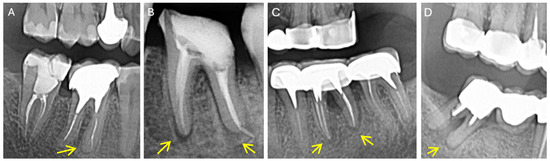

The radiological aspects of combined endo-periodontal lesions (classified according to [26]) are revealed in Figure 2A–D.

Figure 2. Endo-periodontal lesions (without root damage) in endodontically treated teeth with periapical lesions: (A) Grade 1 (4.6.–4.7) (B) Grade 2 (3.6) (C) Grade 3 (3.6.) (D) Grade 3 (4.7) (EPL classification according to Herrera et al., 2018 [26]).